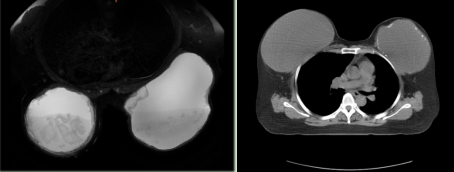

乳房假體CT圖

患者入院后,經過周密的術前檢查,確認王女士符合手術指征。經與患者及家屬溝通,決定為王女士行腔鏡輔助下雙側乳房假體取出術。覃勇副主任醫師表示,腔鏡輔助下乳房假體取出術與傳統手術相比具有許多優點,包括切口更小、創傷更小、術后恢復更快。2月5日,甲狀腺乳腺外科團隊成功為患者在腔鏡下取出置入了乳房30多年的假體,手術十分順利,患者術后恢復良好,對手術效果非常滿意。